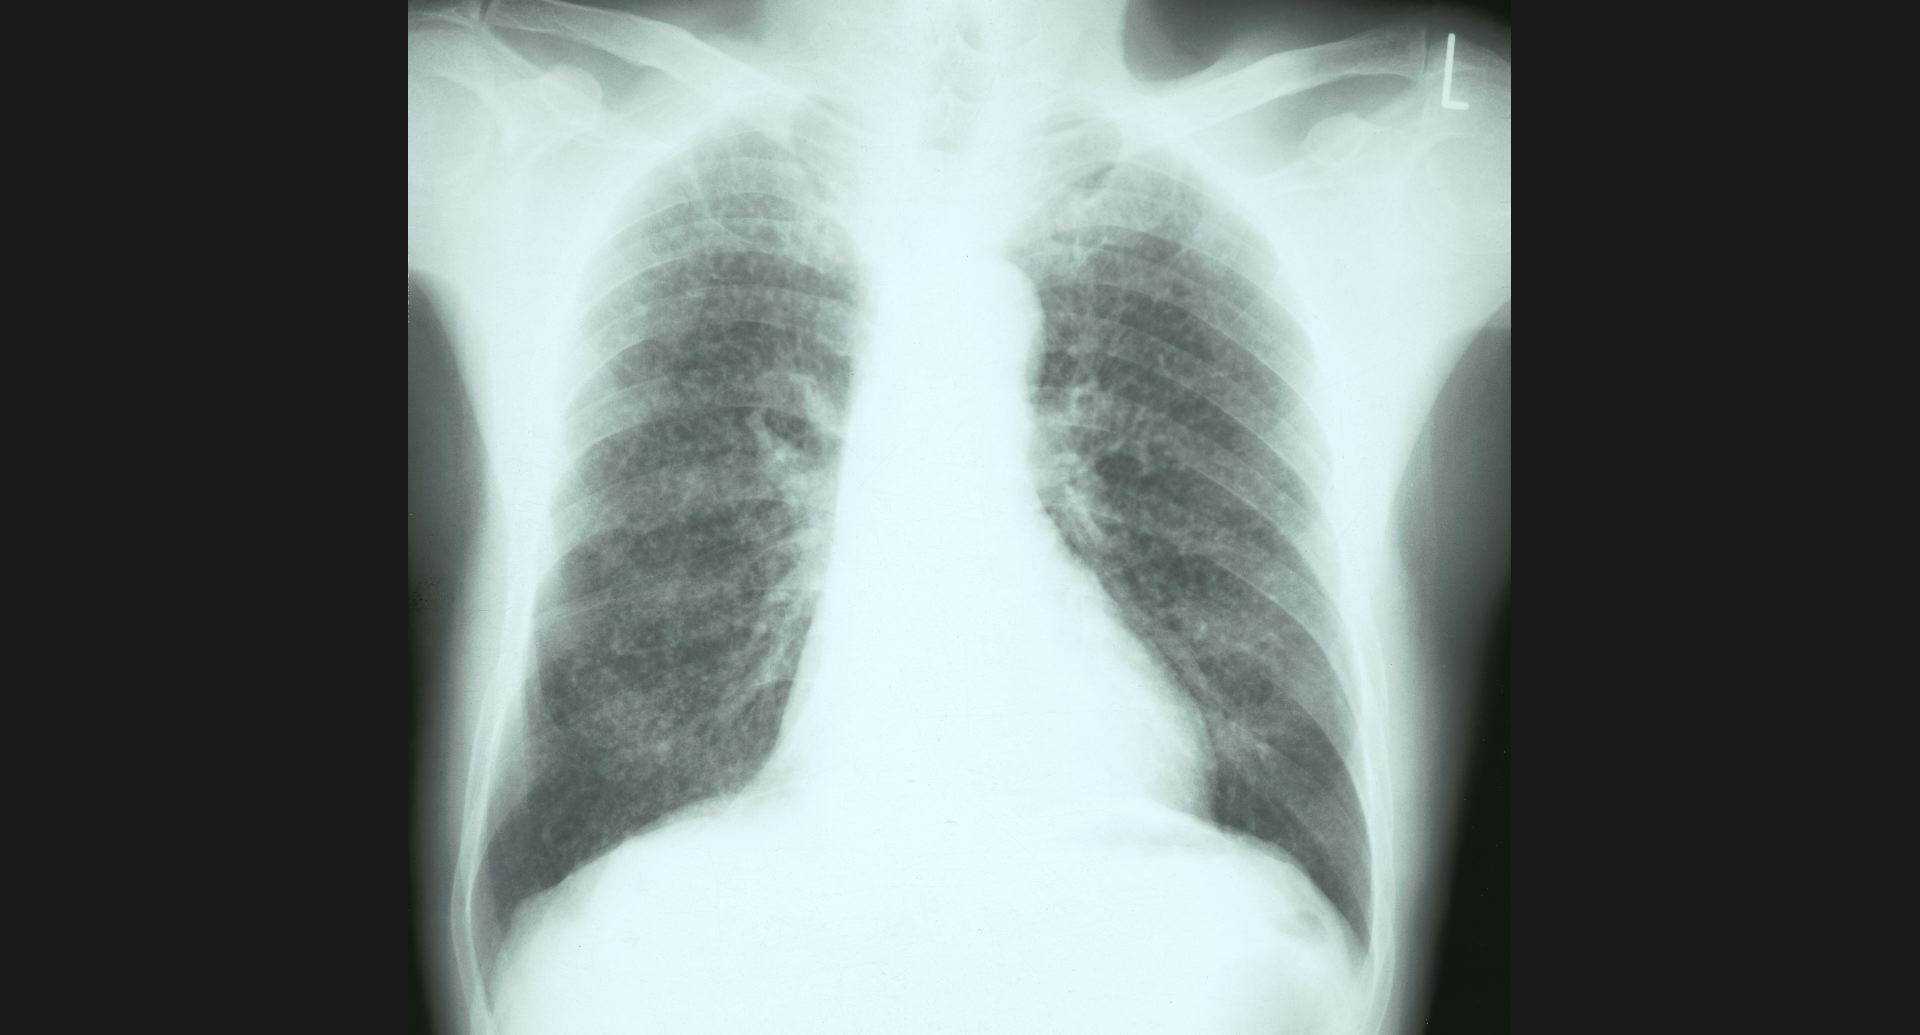

fig.1(117KB)

:Alveolar microlithiasis細かい肺病変、air bronchogram。